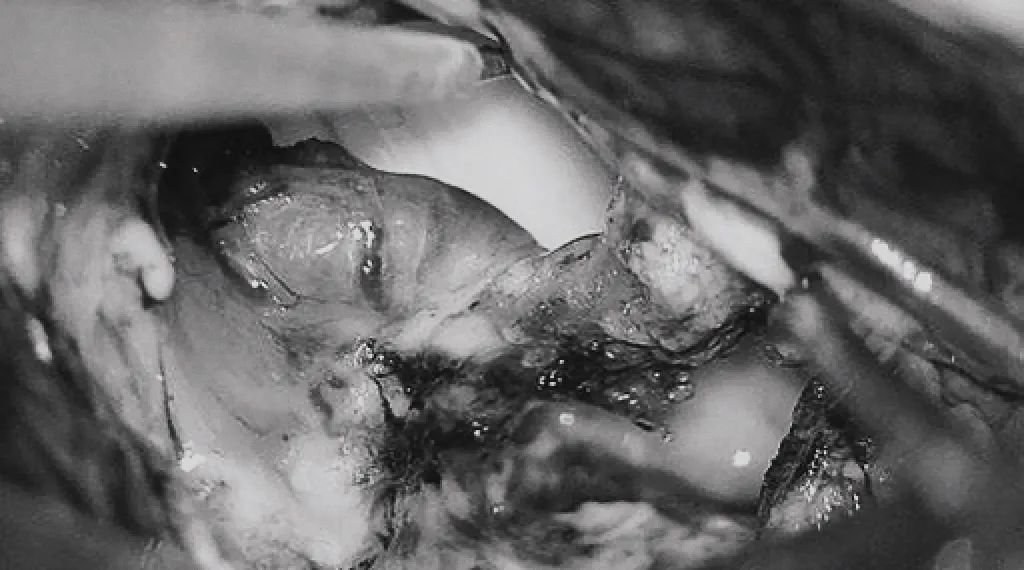

▼(g)引流静脉变黑。